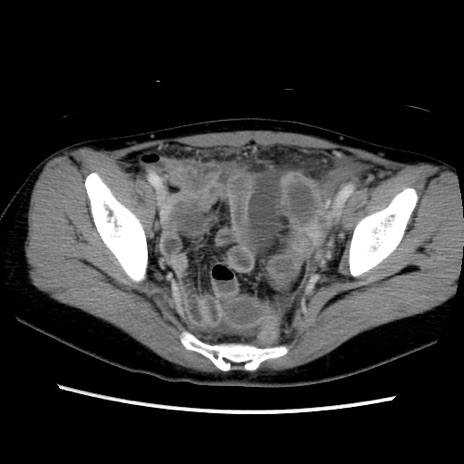

症例39(横断像)

【症例】40歳代女性

【主訴】上下腹部痛

【現病歴】2日目から下腹部痛あり。夜間は痛みで眠れなかった。昨日より上腹部痛と下痢が出現。臥位で痛みは軽快したため、休んでいた。本日になって臥位でも立位でも痛みが強くなってきたため救急要請。

【既往歴】子宮内膜症

【身体所見】部:平坦・軟、左上下腹部に圧痛あり、反跳痛あり。

【データ】WBC 21800、CRP 26.78